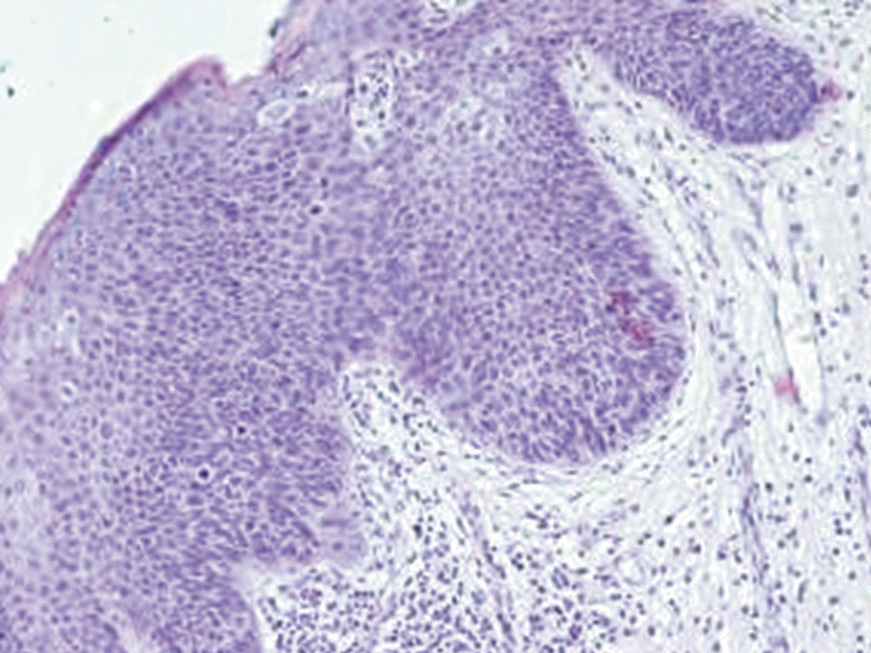

In Group B patients, the hyperplastic epithelium demonstrated focal proliferation of epithelial cells with hyperchromatic polymorphic nuclei against a background of acanthotic, papillomatous, and dystrophic features. These changes included loss of polarity, partial disruption of epithelial stratification starting from the basal layer and extending to upper layers, involving areas of varying size and epithelial thickness. Low-grade dysplasia was diagnosed in 6 patients, high-grade dysplasia in 16 patients, among which 5 cases (31.3%) showed combined foci of low- and high-grade dysplasia, and 6 cases (37.5%) revealed areas of covering epithelium ulceration with marked reactive inflammation in the subepithelial stroma manifested by diffuse infiltration of segmented leukocytes, lymphocytes, and histiocytes along with occasional eosinophilic granulocytes and macrophages. In specimens with intact epithelial lining, mixed inflammatory cell infiltration of the lamina propria was also observed, varying in intensity and cellular composition. The epithelial changes characteristic of Group B patients are illustrated in Figures 2 and 3.

Figure 2. Changes in the lip mucosa at the lesion site in Group B patients. Hyperplasic squamous epithelium has high-grade dysplasia with intra- and subepithelial lymphocytic infiltration. Staining with hematoxylin and eosin. ×200.

Рисунок 2. Изменения слизистой оболочки губы в очаге повреждения у пациентов группы Б. В гиперплазированном многослойном плоском эпителии дисплазия высокой степени тяжести с интра- и субэпителиальной лимфоцитарной инфильтрацией. Окраска гематоксилином и эозином. ×200.